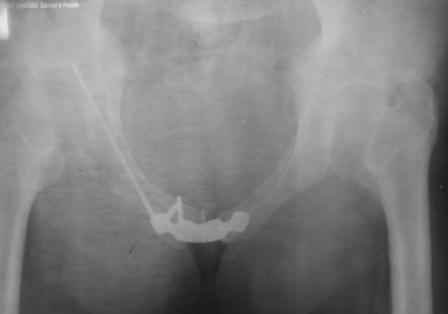

Re: закрытый остеосинтез лонной кости винтом

в архиве нашел подобный случай

С Уважением А.Миронов(Новокузнецк)